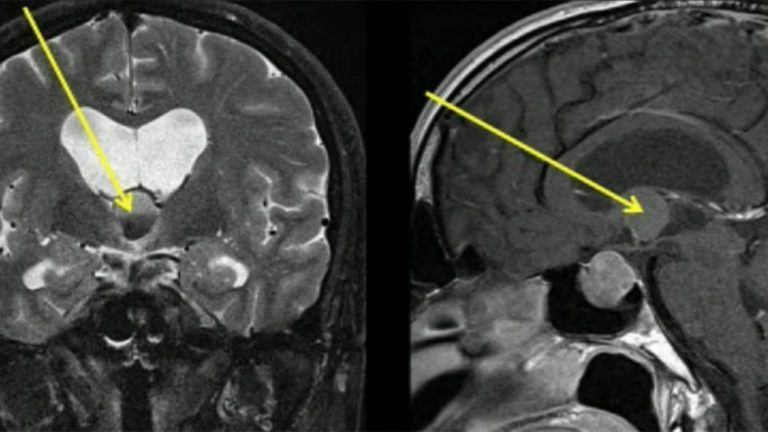

scan of a brain

Endoscopic Colloid Cyst Resection